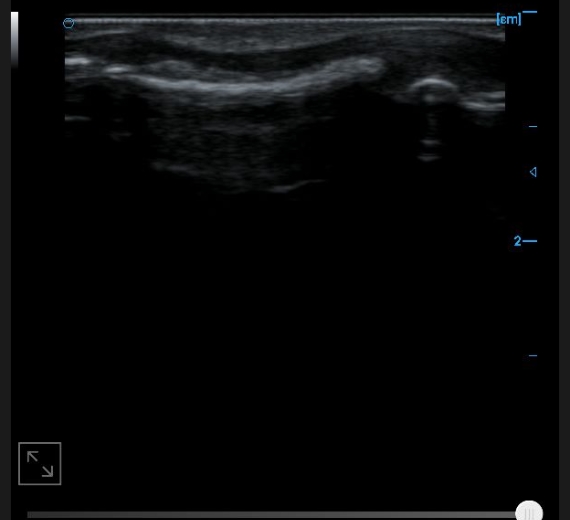

Knee collateral ligament B image